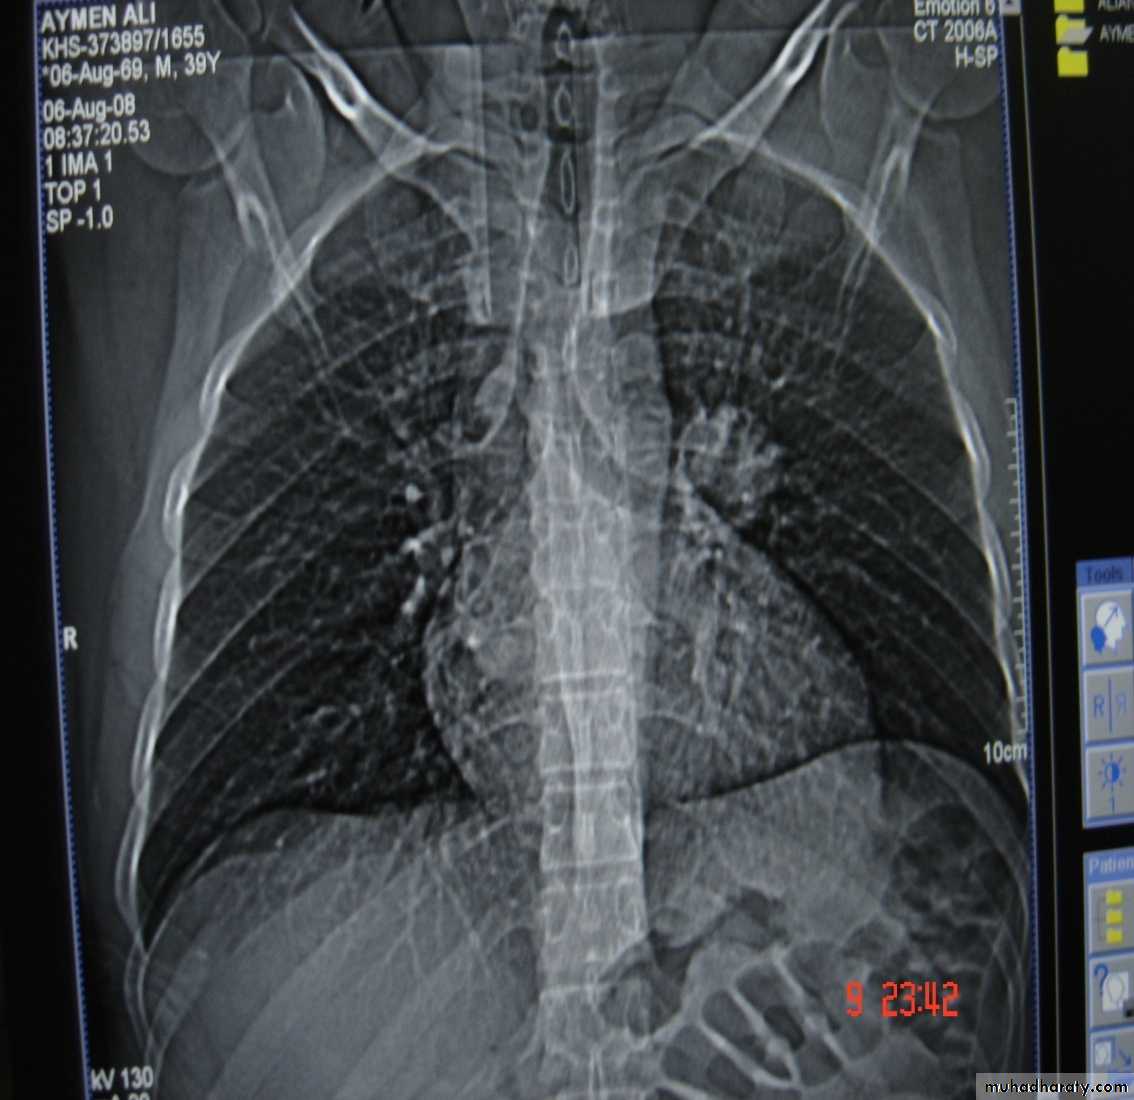

• Pulmonary Echinococcosis (Hydatid Cyst)

• Hydatid disease of the lung is caused by the small tape worm (Taenia Echinococcus ) or (Echinococcus Granulosis) .Hydatid cyst means cyst full of water .It has a life cycle between dogs & sheep .Parasites in the elementary tract of the dog shed ova that excreted in the dog faeces , contaminated the food of the sheep in which hydatid cyst will develops in the viscera . Including the lung .Infected sheep when slaughtered and its entrails are eaten by dogs , the life cycle is completed .When a human being hands or food become contaminated with canine fecal material containing ova which will be ingested .The parasitic larva burrow through the gastric mucosa and are carried to the liver in the portal venous circulation where most of them filtered out to form hydatid cyst of the liver , some escape the liver & lodge in the lung to form one or more hydatid cyst which grows slowly or rapidly over years .

• The cyst consists of a germinal layer & cyst fluid containing broad capsule & scoleses . A cellular white hyaline layers are laid down outside the cyst so that the cyst is enclosed by a laminated cyst membrane .As the cyst enlarged , it usually reaches the pleural surface . Compression of the lung tissues produces a thin fibrous layer of atelectatic lung tissue around the cyst (capsule , pericyst or adventia)

• A-Asymptomatic• Any smooth homogenous opacity of uniform density with clear cut border and little or no reaction around it on a chest X-Ray is a hydatid cyst unless proved the other wise .

• Radiological Findings

• 1-Smooth homogenous opacity (Intact H.C).• 2-Partial rupture (per vesicular pneumocyst).

• 3-Complete rupture (Water –lilly sign) .